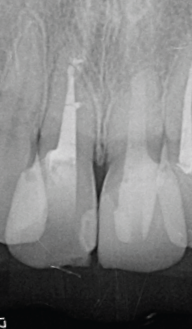

術後5年経過、根尖周囲の透過像も軽減し、CBCT像では喪失していた唇側の皮質骨の再生が認められる(図14・15)。

<術後5年後のレントゲン像とCBCT像>

左上1番の根尖周囲の歯周組織も再生が認められ、

右上1番の根尖部歯周組織も安定している

(図14)

(図15)